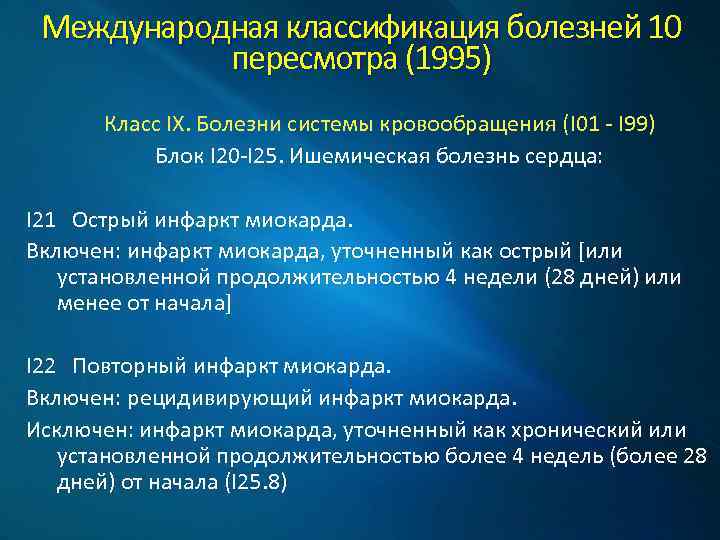

Международная классификация болезней 10 пересмотра (1995) Класс IX. Болезни системы кровообращения (I 01 - I 99) Блок I 20 -I 25. Ишемическая болезнь сердца: I 21 Острый инфаркт миокарда. Включен: инфаркт миокарда, уточненный как острый [или установленной продолжительностью 4 недели (28 дней) или менее от начала] I 22 Повторный инфаркт миокарда. Включен: рецидивирующий инфаркт миокарда. Исключен: инфаркт миокарда, уточненный как хронический или установленной продолжительностью более 4 недель (более 28 дней) от начала (I 25. 8)